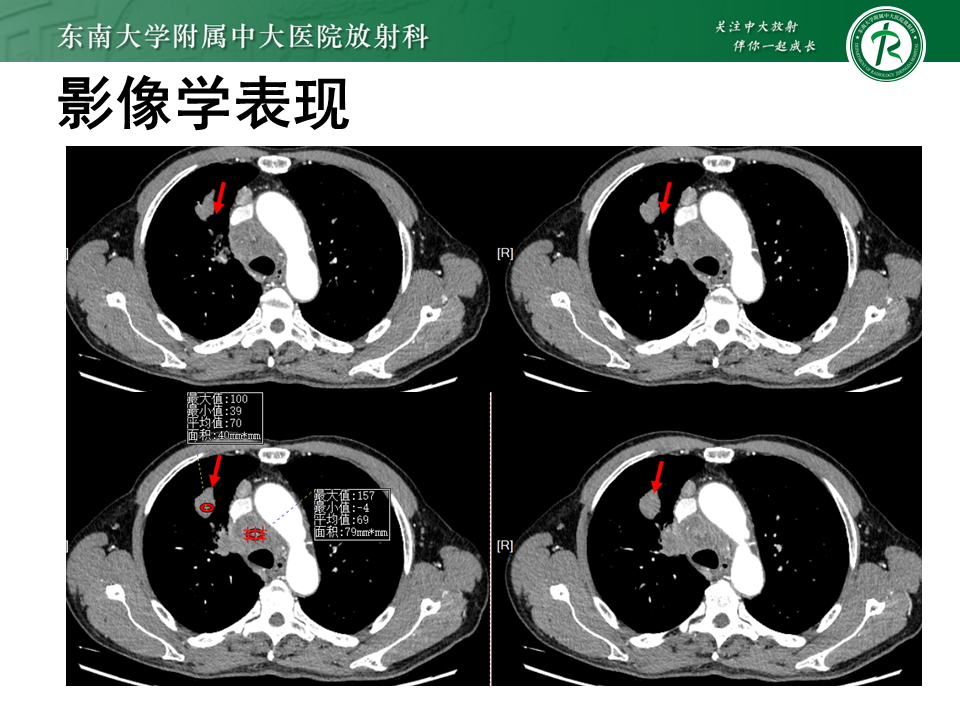

• 影像学检查:3536585,2025-11-10 胸部CT增强

影像学表现

图片来源:东南大学附属中大医院放射科